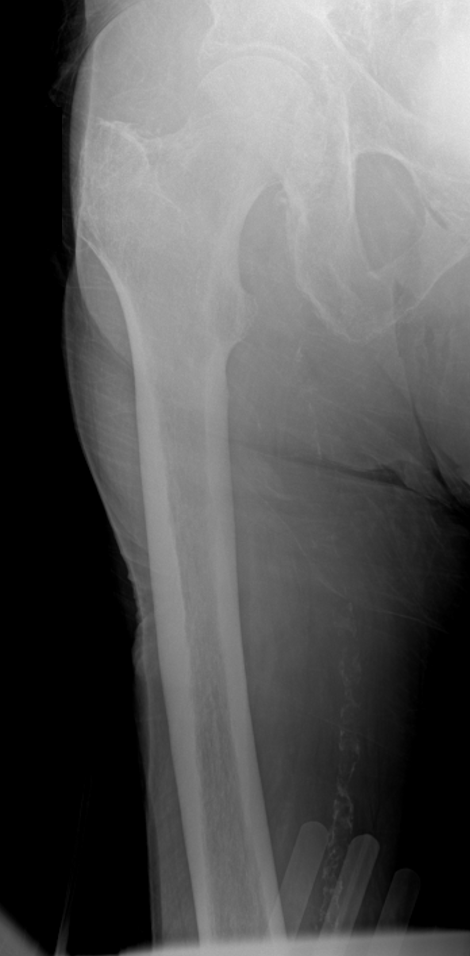

An 86-year-old male after a low-energy fall onto the right knee with a periprosthetic distal femur fracture above a TKA. These cases are getting more common, and the real challenge is not whether to operate—it’s choosing the construct. Nail? Plate? Dual plate? Nail-plate combo? Or do you skip fixation and replace it? For me, the decision tree starts with 3 questions: 1. Is the femoral component stable? 2. Is the femoral box actually nail-compatible? 3. Is the distal segment/bone stock strong enough for single-implant fixation? What would you do here? @orthobullets @medbullets orthobullets.com/Site/Cases/Vie…

Jan Szatkowski tweet mediaJan Szatkowski tweet mediaJan Szatkowski tweet media